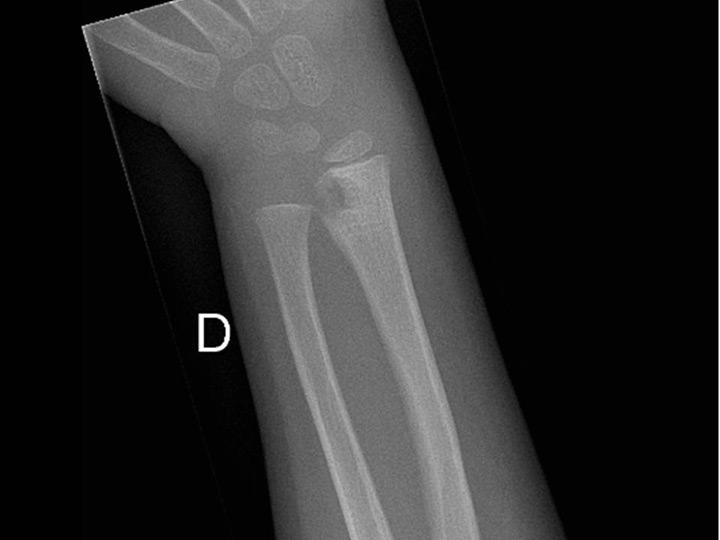

Figure 4

Sub-acute transphyseal osteomyelitis of the distal radius due to K. kingae in a 5-year-old boy who suffered from a chickenpox (varicella) infection three weeks before bone infection. This viral infection was considered as a predisposing factor for the development of osteomyelitis due to K. kingae resulting from a modulation of the immune system function.

The incidence and prevalence of paediatric tuberculosis worldwide varies significantly according to the burden of the disease in different countries. Europe and North America are traditionally considered as low burden regions, and paediatric incidence rates vary from 1 to 15/100,000/year [78]. Tuberculosis of bones or joints occurs in around 5% in cases of paediatric extrapulmonary tuberculosis and, classically, tubercular OAIs occur one to three years after pulmonary infection. Vertebral lesions (thoracic>lumbar>cervical) are probably the most common involvement and 80% of these affect more than one vertebrae. In decreasing order, other common sites are: hips; knee; ankle and foot; hand and wrist; elbow; shoulder; bursal sheaths; and other bones [79]. Tubercular OAI is rare, but not exceptional in Switzerland (fig. 4) and it must be considered when a very young child presents a clinical picture of sub-acute osteomyelitis with a mild-to-moderate clinical and biologic inflammatory response to infection. In general, contamination is intra-familial due to close proximity with elderly individuals from regions where the prevalence of tuberculosis is high (e.g., Balkans, Africa, India). Finally, immunocompromised children and those seropositive for human immunodeficiency virus (HIV) are supposed to be at high risk of exposure, as well as manifesting tubercular disease. The synergy of HIV and tuberculosis and the emergence of multidrug-resistant Mycobacterium tuberculosis have further complicated the issue.